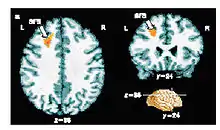

Results from an fMRI experiment in which people made a conscious decision about a visual stimulus. The small region of the brain coloured orange shows patterns of activity that correlate with the decision making process. Crick stressed the importance of finding new methods to probe human brain function.